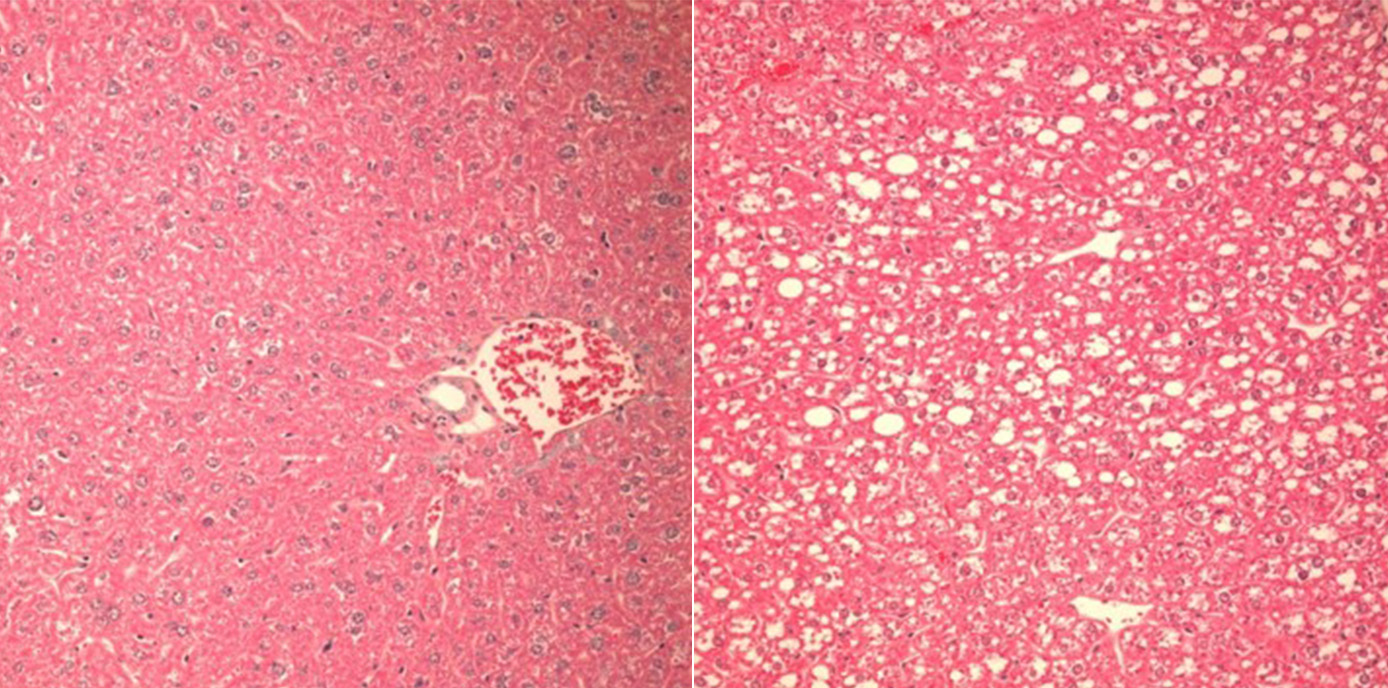

Auch wenn man noch wenig über Auslöser und Art der Caspase-2-Aktivierung in der verfettenden Leber weiß, konnten die Forscher:innen nun zeigen, dass der Verlust des PIDDosoms bei Fruktose-reicher Diät vor der Zerstörung von Leberzellen, Entzündung und Gewichtszunahme schützt. „In unseren Mausmodellen gelang es, den Einfluss des PIDDosoms auf den Lipid-Stoffwechsel und die Entwicklung hin zur Leberentzündung klar darzustellen: War Caspase-2 ausgeschaltet, entwickelten Mäuse trotz Fruktose-haltiger und Fettsäure-reicher Diät keine Leberschädigung, da die Enzyme, die sonst zur Leberverfettung führen, nicht aktiviert wurden“, beschreibt Villunger die zentrale Erkenntnis.

Die Forscher:innen belegen damit die Existenz eines bisher unerkannten Regulationssystems, das die Homöostase der Leber und die Integrität des Endoplasmatischen Retikulums stützt und so den Übergang von einer einfachen Steatose zu einer Steatohepatitis steuert, indem es den Fettsäure- und Cholesterinstoffwechsel entsprechend diätetischen Herausforderungen anpasst.

(29.09.2022, Text: D. Heidegger, Bild: V. Sladky )